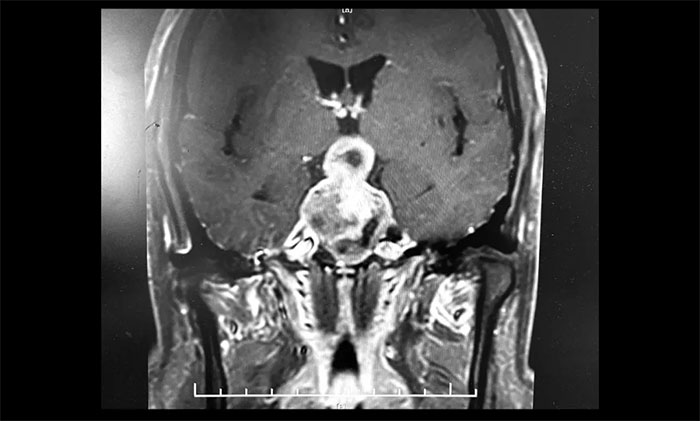

▲ 5公分巨大垂体瘤,呈“哑铃”形,李士其教授团队迎难而上顺利切除

李士其教授分析,对于病变已经侵袭海绵窦,单纯采用以往经鼻入路或经颅入路的术式均难以全切肿瘤,并且颈内动脉损伤的风险极大。如何将颈内动脉损伤风险降到最低,又能尽可能全切肿瘤?一般考虑采用经蝶和经颅联合入路手术策略切除肿瘤。

目前联合入路切除垂体瘤通常有两种方式,一是采用联合入路一次手术实现肿瘤全切除,二是分次手术以达到肿瘤切除的目的。李士其教授介绍,此类手术,对患者的视力保护极其重要,对于巨大垂体瘤难以一次性手术切除的肿瘤,可以先行一次手术,然后在数周或数月后执行进行二次手术,即经蝶和经颅联合入路分次手术策略。